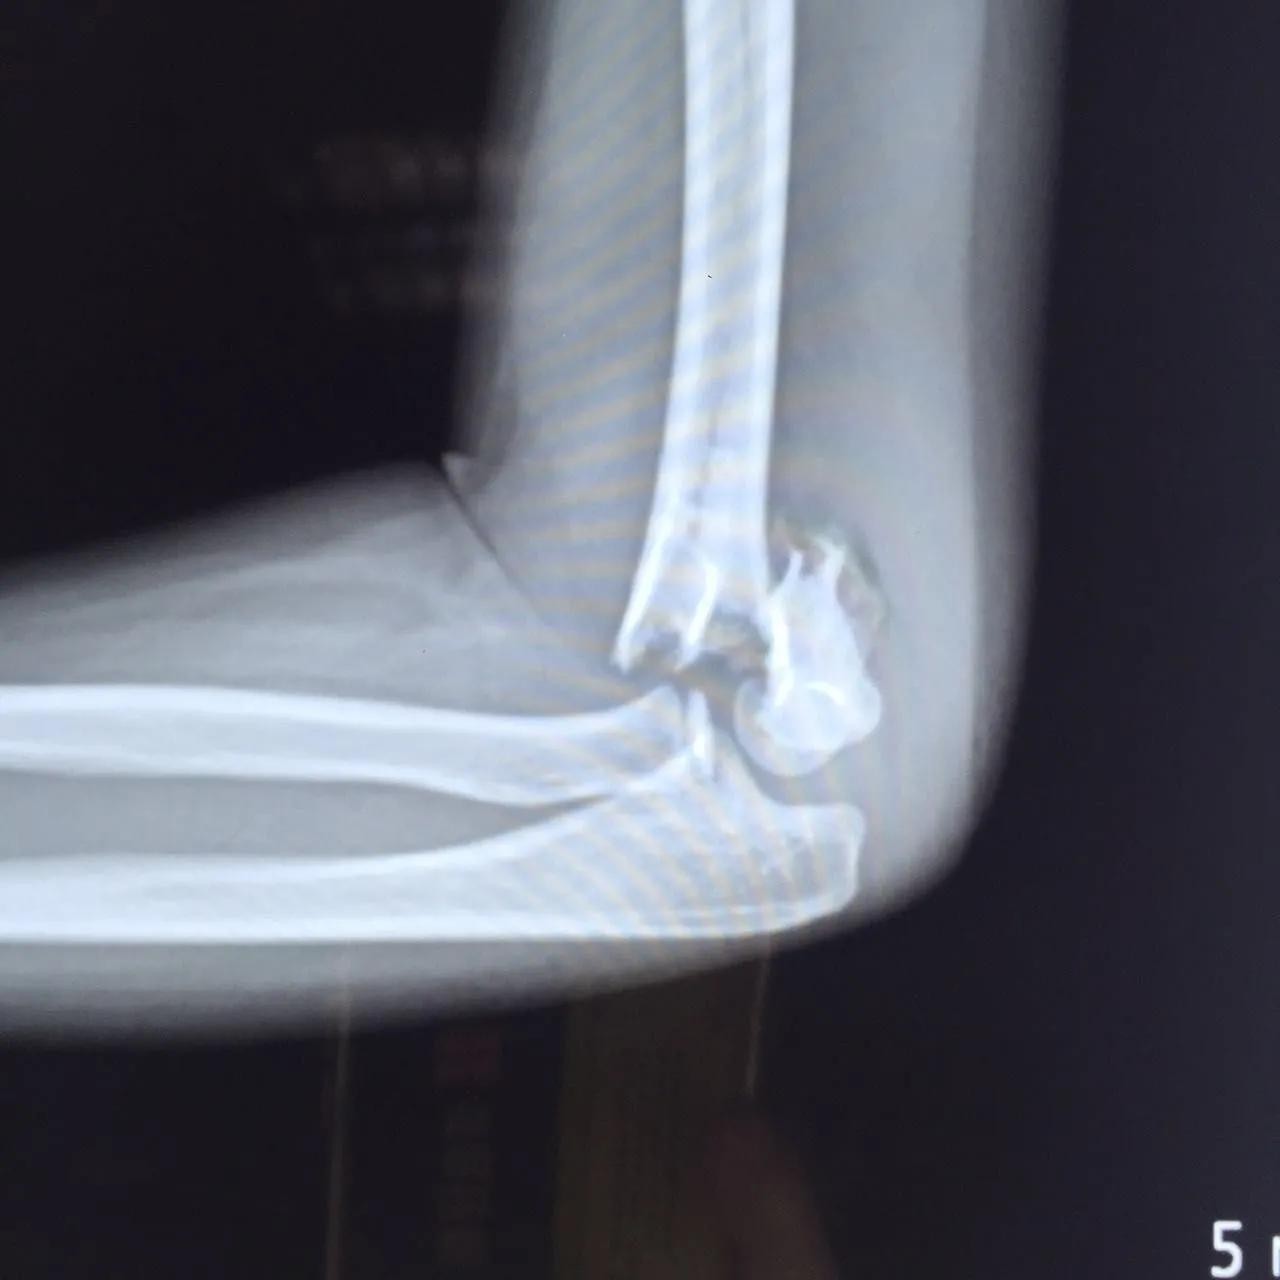

四、肱骨骨折X线图

肱骨骨折根据发生部位的不同分为肱骨外科颈、肱骨干、肱骨髁上、肱骨髁间、肱骨外髁、肱骨内上髁。